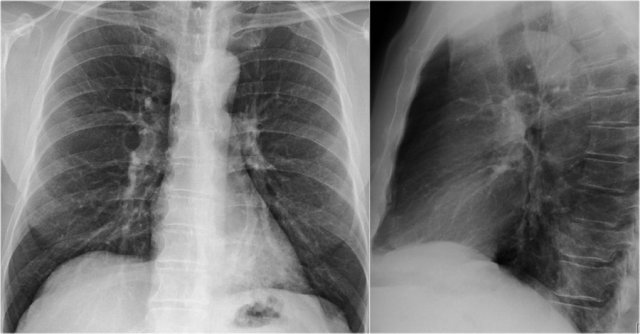

• Case Example

A patient with bilateral carcinomatous pleuritis.

Findings

• Complete opacification of the right hemithorax.

• Air bronchogram in the right main bronchi (arrowheads), indicating compression atelectasis of the lung due to massive effusion.